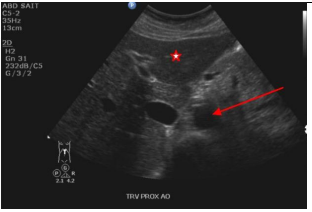

10

Q

Label the red, blue, and yellow arrows

A

Red: Body of pancreas

Blue arrow: IVC

Yellow: Splenic vein